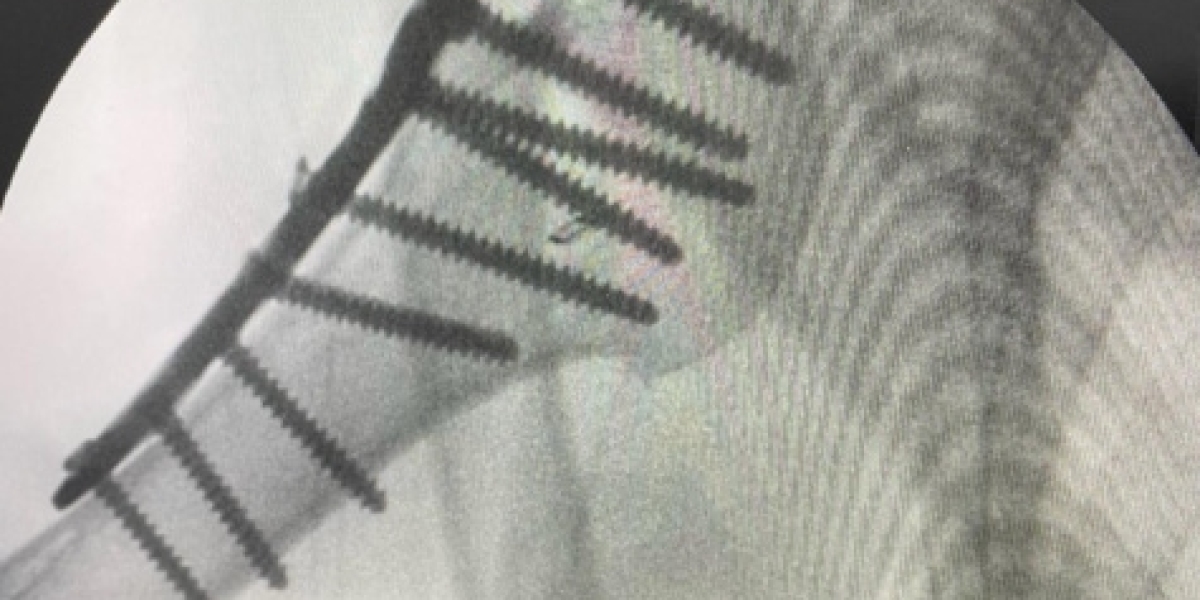

Open Reduction Internal Fixation Surgery: Trusted Treatment from an Expert Orthopedic Surgeon in London | #open Reduction Internal Fixation Surgery #orthopedic Surgeon in London

Open Reduction Internal Fixation Surgery: Trusted Treatment from an Expert Orthopedic Surgeon in London

If you've experienced a serious fracture that can't be treated with a simple cast, Open Reduction Internal Fixation Surgery may be the best route to full recovery. This advanced procedure can restore proper bone alignment, improve function, and speed up your return to normal li